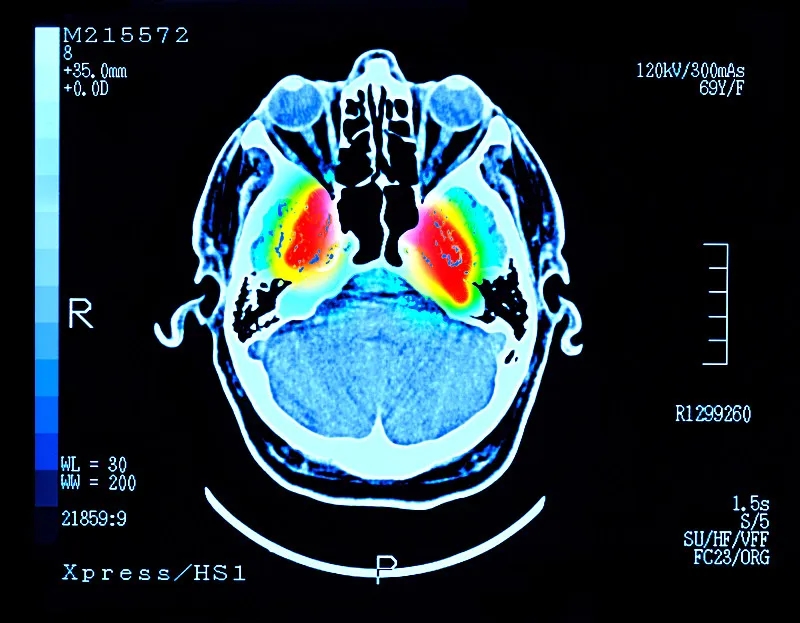

帕金森病 (PD) 是大腦中的一種疾病,它會(huì)殺死產(chǎn)生一種叫做“多巴胺”的化學(xué)物質(zhì)的神經(jīng)元。多巴胺是一種重要的化學(xué)物質(zhì),負(fù)責(zé)大腦內(nèi)神經(jīng)元之間的交流。細(xì)胞死亡主要發(fā)生在“黑質(zhì)”,這是大腦中主要的多巴胺產(chǎn)生區(qū)域。

這些治療可緩解帕金森病的癥狀,但不會(huì)減緩或逆轉(zhuǎn)大腦神經(jīng)細(xì)胞的損傷。隨著時(shí)間的推移,盡管進(jìn)行了治療,但臨床特征會(huì)變得更糟。當(dāng)患者被診斷出患有帕金森癥時(shí),他們通常已經(jīng)患病多年,并且黑質(zhì)內(nèi)的多巴胺細(xì)胞已經(jīng)丟失了一半以上。早期檢測(cè)帕金森癥的測(cè)試可能有所幫助,但科學(xué)家們正在尋找一種方法來(lái)替換受損的細(xì)胞。